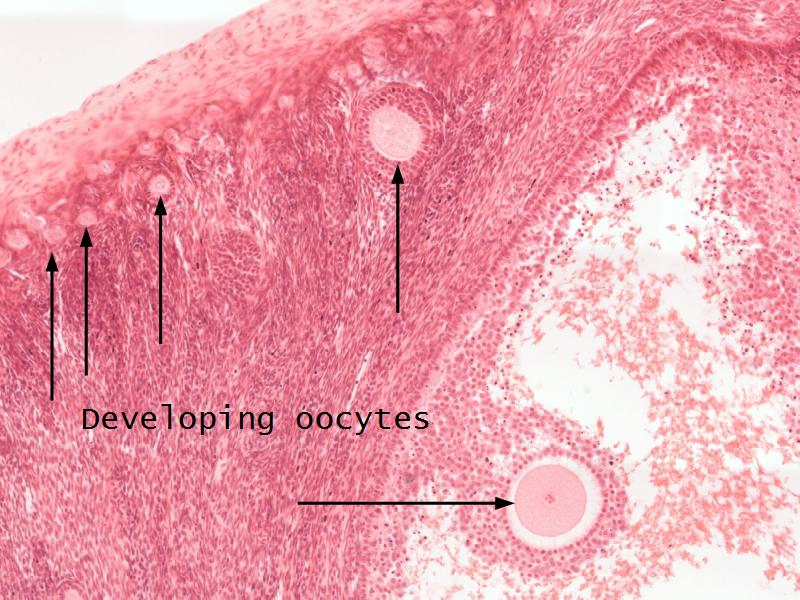

- Ovary

- F3: Granulosa cell

- F3: Granulosa cell = ovarian follicle

- Slide 89/106: Ovary